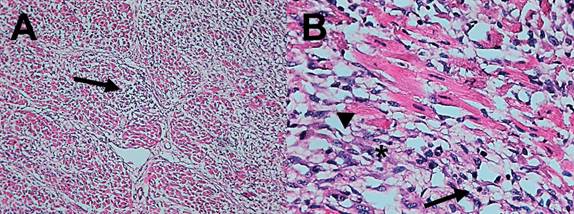

In the necropsies performed, the main macroscopic findings consisted of degenerative myopathy with multifocal whitish areas in the heart (Figure 1), hydrothorax (Figure 2), hydropericardium, congestion, and pulmonary edema, these alterations were reported as a consequence of heart failure. Similar lesions have been found in other reports of ionophore poisoning (Andrade et al., 2020; Bence et al., 2018; De La Cruz-Hernandez et al., 2012; Rozza et al., 2006). From the most important organs, samples were taken for histological evaluation, which revealed that the main lesions were found in the heart, lung, and liver. Of the necropsied calves, 100% showed suppurative or non-suppurative myocarditis with degeneration of myocardial fibers (Figure 3). Suppurative and necrotic hepatitis was found in the liver. 100% presented some type of fibrinous, suppurative, or fibrinopurulent bronchopneumonia with fibrinous pleuritis and necrotic vasculitis. 55.55 % showed fibrinoid arteritis and 55.55 % pulmonary congestion and edema. Cardiac tissue is one of the most affected organs due to its high kinetic activity, and the liver is affected due to congestion and to the fact that ionophore metabolism takes place in this organ. Heart and liver alterations have been previously reported with similar lesions (Andrade et al., 2020; Bence et al., 2018; De La Cruz-Hernández et al., 2012; Omidi et al., 2008). However, lung damage is atypical in this type of poisoning. The greatest possibility is that it is an isolated event since these lesions have not been reported previously. The absence of previous respiratory infections in the exposed animals and the finding of pulmonary alterations in all the calves studied suggests that it could be related to the poisoning, probably due to systemic inflammatory response syndrome (SIRS). However, given the absence of a control group, we cannot fully conclude with this finding. It is suggested that emphasis should be placed on lung tissue damage for future reports.